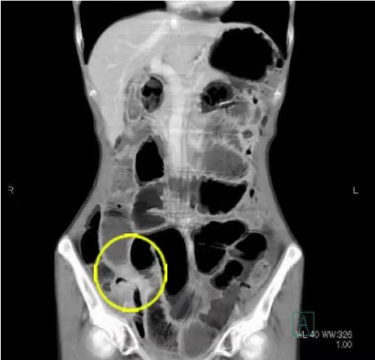

手術前の検査(CT検査)

CT写真の黒い部分が空気です。左側の写真では腸閉塞で太く腫れあがっている腸でおなかの中が充満しています。

別の断面の写真(右側)では癒着により細くなった腸管を認めます(◯)。ここが腸閉塞の原因だとわかります。